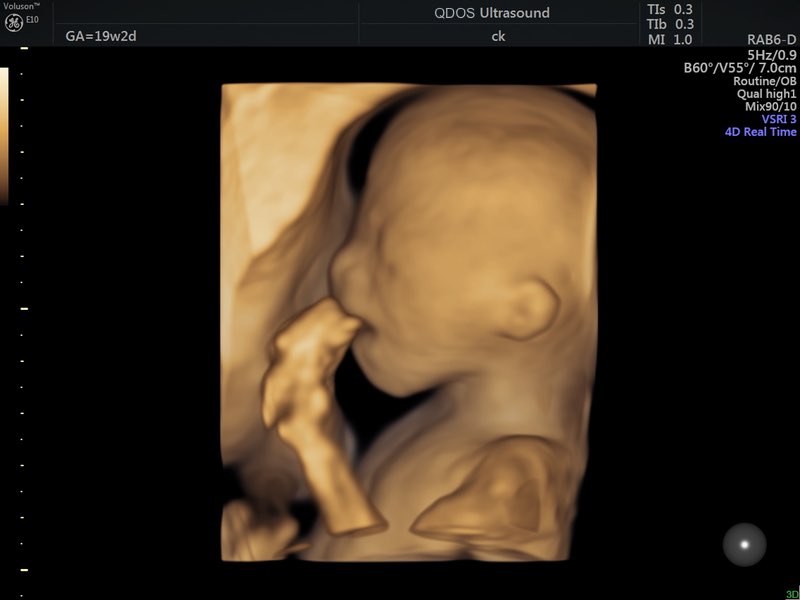

All machines at QDOS Ultrasound in Perth are 3D/4D capable.

At QDOS Ultrasound, we use top model GE ultrasound machines, known for their exceptional image quality and advanced technology. These machines enable our experienced team to provide highly detailed and accurate assessments, ensuring you receive the best possible care throughout your pregnancy journey. They also have excellent 3D/4D capability.

In ‘2D’ ultrasound, only a thin slice of the fetus is viewed at any one instant. This allows a lot of detail, and the person performing the ultrasound (the sonographer) mentally gets the third dimension by moving the probe. With 3D ultrasound, a whole series of slices are taken in quick succession. The slices are then put together to look more like a picture you would see with your eyes. To get the rapid multiple slices, each individual ultrasound slice contains diluted information.

4D is a description of 3D that tells you it is being performed live. Therefore, the fetal movement is seen.

The quality of 3D and 4D images depends on several factors, including the baby’s position, the amount of fluid around the face, and whether limbs or the umbilical cord are blocking the view. As with 2D ultrasounds, maternal build can also influence the image quality.

When the conditions are right, seeing your baby’s face in 3D can be an unforgettable experience for parents-to-be. However, it’s good to keep in mind that some minor distortions are a natural part of the imaging process.